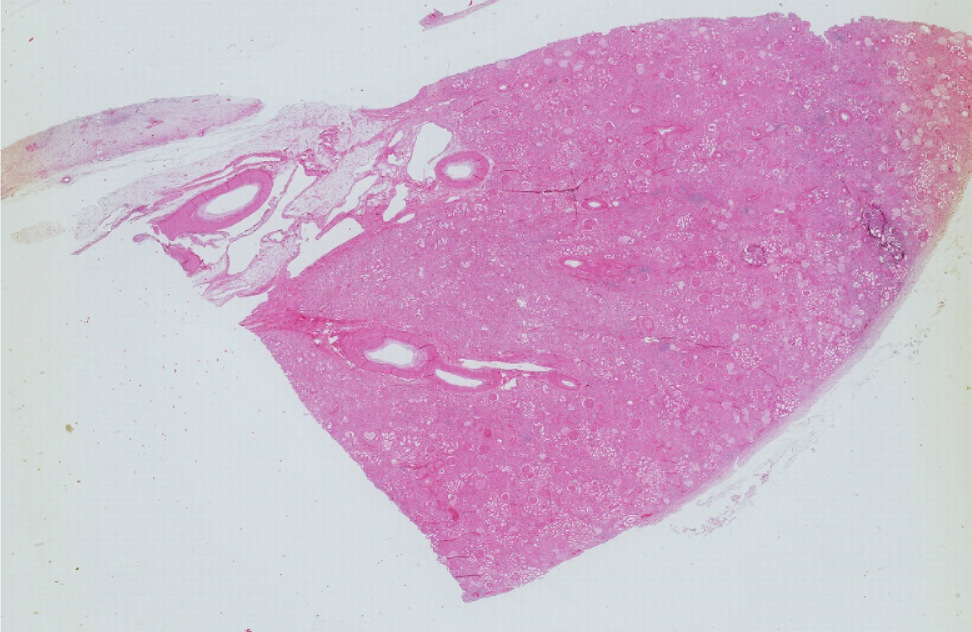

1.全景图